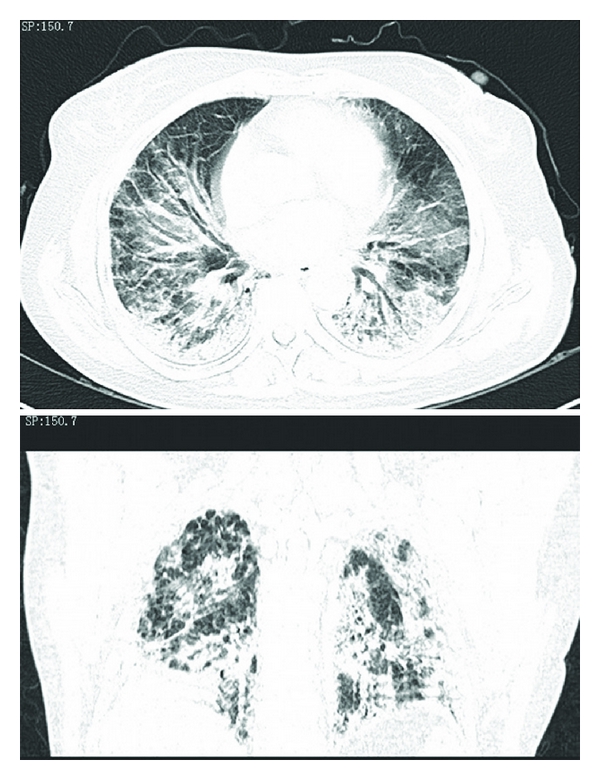

Blood gas analysis revealed Po2 8.54 KPa, Pco2 4.9 KPa, pH 7.421, FiO2/PaO2 = 120. WBCs and HGB were within normal limits. NEU% of 74.1% was slightly increased. Serologic examinations including ANA, Sm, UI-NRnp, Jo-1, Scl-70, SSA, SSB, P-ANCA, RF, C-ANCA, and HIV were all negative. ECG demonstrated sinus tachycardia. Chest radiography was performed which is shown in Figure 1. Her chest CT scan (Figure 2) revealed areas of ground glass attenuation and consolidation in bilateral bases of her lungs accompanied with traction bronchiectasis.

The features of chest radiography from our patient are consistent with typical AIP appearances: progressive, patchy-distributed but not limited to, airspace consolidation and ground-glass attenuation in bilateral lung often diffusely involves the mid and lower zones on X-ray, with the decreased lung volumes. HRCT scan shows bilateral and patchy ground glass attenuation located distinctly at either subpleural or central, leading to a geographic appearance of preserved areas of lung lobules [1, 2]. Consolidation, most common in the dependent area of lung which is seen in the absence of traction bronchiectasis, provides an early radiographic clue to underlying fibrosis [15]. Intralobar linear opacities and subpleural honeycombing may be seen in a minority of cases after the duration of the process continues for more than a month. Later, traction bronchiectasis and architectural distortion which may increase with the duration of the disease [16] are common findings in patients imaged at an organizing stage of disease. Also, cysts and other lucent areas of lung become more common in the late stages of AIP. In reported case, HRCT showed diffused pulmonary infiltration and ground glass attenuation in a geographic appearance, consolidation with associated traction bronchiectasis which confidently fitted into the feature of later phase AIP. The later stage should be another factor to make the pathologic process irreversible even when treated with a steroid pulse therapy.